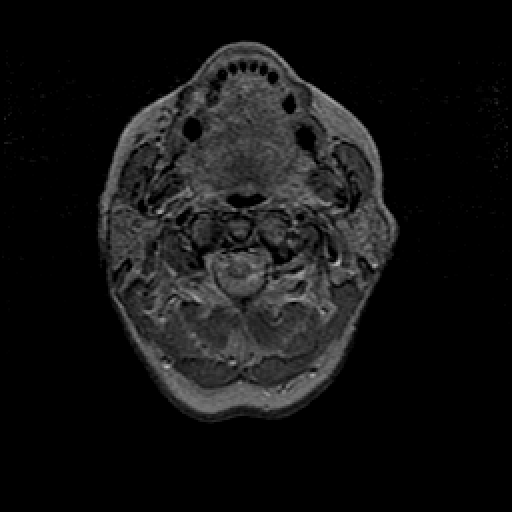

Proton density-weighted structural MR: Slice 1

Slice 1